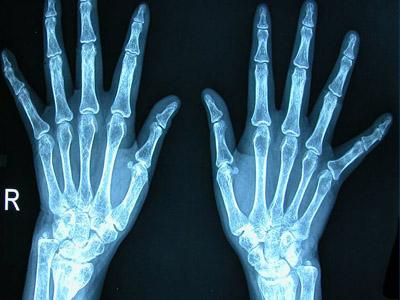

类风湿关节炎(RA)是一种病因未明的慢性、以炎性滑膜炎为主的系统性疾病。其特征是手、足小关节的多关节、对称性、侵袭性关节炎症,经常伴有关节外器官受累及血清类风湿因子阳性,可以导致关节畸形及功能丧失。

1、1987年美国风湿病联盟诊断标准:晨僵≥1小时、3个及3个以上关节受累、受累关节的炎症时间>6周、对称性关节炎、类风湿因子阳性、类风湿结节及双手X线片改变七条诊断标准,达到4条及以上,即可确诊;